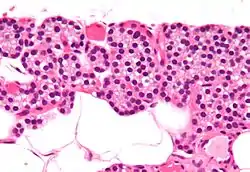

![]() Гістологічна будова паращитоподібної залози (Г-Е) | |

Гістологія

Паратироцити — залозисті клітини, які залежно від функціонального стану залози поділяються на два типи клітин, що мають певні відмінності:

| Назва | Колір | Кількість | Розмір | Функція |

| Головні клітини | темніші | 97% | невеликий | продукують ПтГ (див. нижче). |

| Ацидофільні (оксифільні) клітини | світліші | 3% | великий | невідома |

Головні (базофільні) паратироцити

Утворюють основну частину паренхіми залози. Це дрібні полігональної форми з базофільною цитоплазмою, по периферії якої розсіяні скупчення вільних рибосом, добре розвинута гранулярна ендоплазмотична сітка, комплекс Гольджі, що свідчить про високу інтенсивність білкового синтезу. Серед головних паратироцитів розрізняють світлі та темні клітини, які віддзеркалюють стани функціональної активності прищитоподібних залоз. Темні клітини — активно функціонуючі клітини, цитоплазма яких містить добре розвинутий синтетичний апарат. В їх цитоплазмі багато лізосом та гранул глікогену. Співвідношення неактивних і активних головних паратироцитів зміщене у бік перших і становить 3:1.

Ацидофільні паратироцити

Рівномірно розподілені в паренхімі залози і розташовуються серед головних клітин. У цитоплазмі цих клітин містяться великі мітохондрії, слабко розвинутий комплекс Гольджі, помірно розвинута ендоплазматична сітка, секреторні гранули відсутні. З віком кількість цих клітин збільшується.